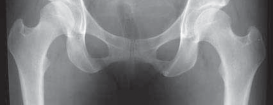

10.

A properly centered anteroposterior pelvis radiograph is essential for assessing the morphology of the hip and comparing the affected to the unaffected side ( FIG 3).

11.

The optimal lateral view has yet to be determined, but a standardized reproducible lateral radiograph of the affected hip should be obtained in every case.

12.

Radiographs usually are normal with regard to specific findings indicative of soft tissue pathology in the hip.

13.

The soft tissue disease usually is far advanced before any radiographic indices emerge.

14.

Thus, it is important to scrutinize the radiographs carefully, assessing for subtle indicators of change.

1.

For example, slight joint space narrowing usually indicates advanced intra-articular disease, and should be viewed

---

### FIG 3 • An AP radiograph allows comparison of the affected and unaffected hips as well as an assessment of the surrounding bony architecture. It must be properly centered without rotation to assess the radiographic indices of hip morphology accurately. (Courtesy of J. W. Thomas Byrd, MD.) as a cautious indicator in counseling patients on the role of arthoscopy.